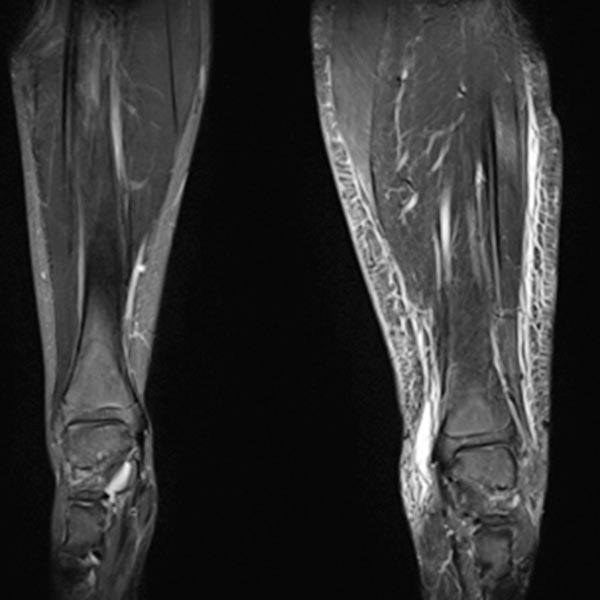

Zusammengesetzte, T1-gewichtete koronare MRT vom Becken bis zu den Füßen. Gut sichtbar hier nicht nur die Beinlängendifferenz (ossäre Hyperplasie), sondern auch die links deutlich größere Muskulatur und das vergrößerte Fettgewebe. Die Hyperplasie der Extremität betrifft beim Parkes-Weber-Syndrom alle Gewebe.

Koronare, T2-gewichtete, fettunterdrückte MRT der Unterschenkel beidseits. Auf der betroffenen linken Seite ausgeprägtes subkutanes Ödem durch den chronischen Venenhochdruck.